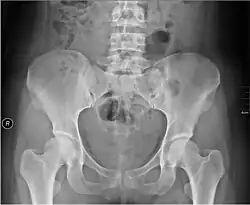

Folgewirkungen einer traumatischen Geburt können Baby und Mutter betreffen. Geburtstraumen gelten als selten in der westlichen Welt verglichen mit entsprechenden Häufigkeiten in der Dritten Welt. Im Westen entstehen Geburtsfolgeschäden bei 1,1 % der Geburten.[3] Zahlreiche körperliche Bedingungen erhöhen die Wahrscheinlichkeit für das Auftreten von Geburtsschäden, darunter:

- Missverhältnis zwischen kindlichem Kopf und Becken der Mutter

- (selten ein) enges Becken

Die Geburt des Menschen ist geprägt von körperlichen Besonderheiten, die im evolutionären Prozess der Hominisation entstanden sind. Bei der Entwicklung des aufrechten, zweibeinigen Ganges entstand eine Vielzahl von Veränderungen des Skeletts und der Skelettmuskeln. Im Zusammenhang mit der Geburt sind insbesondere die Anpassungen der Wirbelsäule und des Beckengürtels relevant.[9] Der so entstandene Beckenkanal, den der Fötus bei der Geburt durchqueren muss, ist im Vergleich mit allen anderen Menschenartigen sehr eng. Seine Innenmaße sind nahezu identisch mit der Kopfgröße des Neugeborenen. Infolge des evolutionären Wachstums des Gehirns (Zerebralisation) ist der menschliche Schädel im Vergleich zu den Schädeln anderer Primaten sehr groß.[10] Auch die Breite der Schultern spielt hier eine größere Rolle, übertrifft sie doch die Breite des fötalen Schädels.[11] Das evolutionär entstandene Verhältnis von Schädelgröße des Kindes und Größe des Beckenrings der Mutter führt dazu, dass „Mutter und Neugeborenes ein beträchtliches Risiko für eine traumatische Geburt“ tragen.[12][13][14]

Beim Geburtsvorgang müssen sich der große Kopf und die breiten Schultern durch den relativ engen Geburtskanal bewegen. Der Geburtsvorgang blieb zwar ein normaler biologischer Vorgang, aber wegen der erwähnten evolutionären Besonderheiten ergibt sich eine besonders komplizierte Geburtsmechanik, die jede Geburt schwierig macht. Der kindliche Kopf muss dabei eine komplizierte Schraubenbewegung durch das mütterliche Becken ausführen.[15] Dabei kann das Kind steckenbleiben, insbesondere wenn aufgrund eines besonders ausgeprägten Missverhältnisses zwischen mütterlichem Becken und kindlichem Kopf die Vorwärtsbewegung nicht angemessen erfolgen kann. Das empfindliche Gehirn des Kindes wird von den beweglichen Knochenplatten des Schädels geschützt. Ein Verknöchern erfolgt erst nach der Geburt. Der menschliche Schädel entwickelte auf diese Weise evolutionär die Besonderheit der Verformbarkeit, damit der vaginale Geburtskanal passiert werden kann.[16] Diese Verformungen finden wohl an einer evolutionsbiologisch erreichten Grenze statt und gefährden das Gehirn des Kindes. Die oben erwähnten möglichen Verletzungen des Schädels und des Gehirns sind Folge dieser anatomischen Besonderheiten.